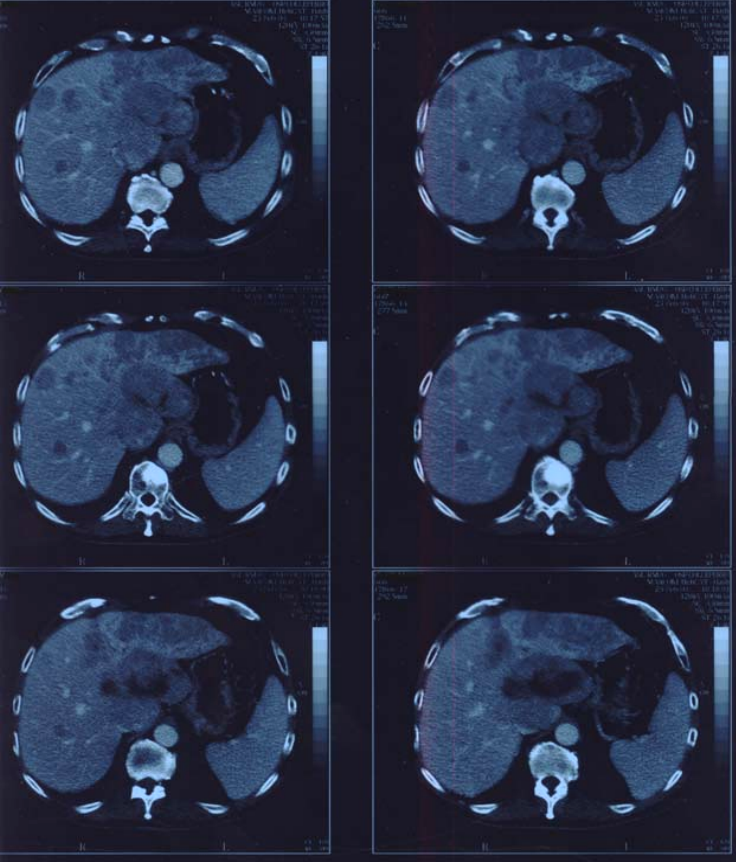

Figure3